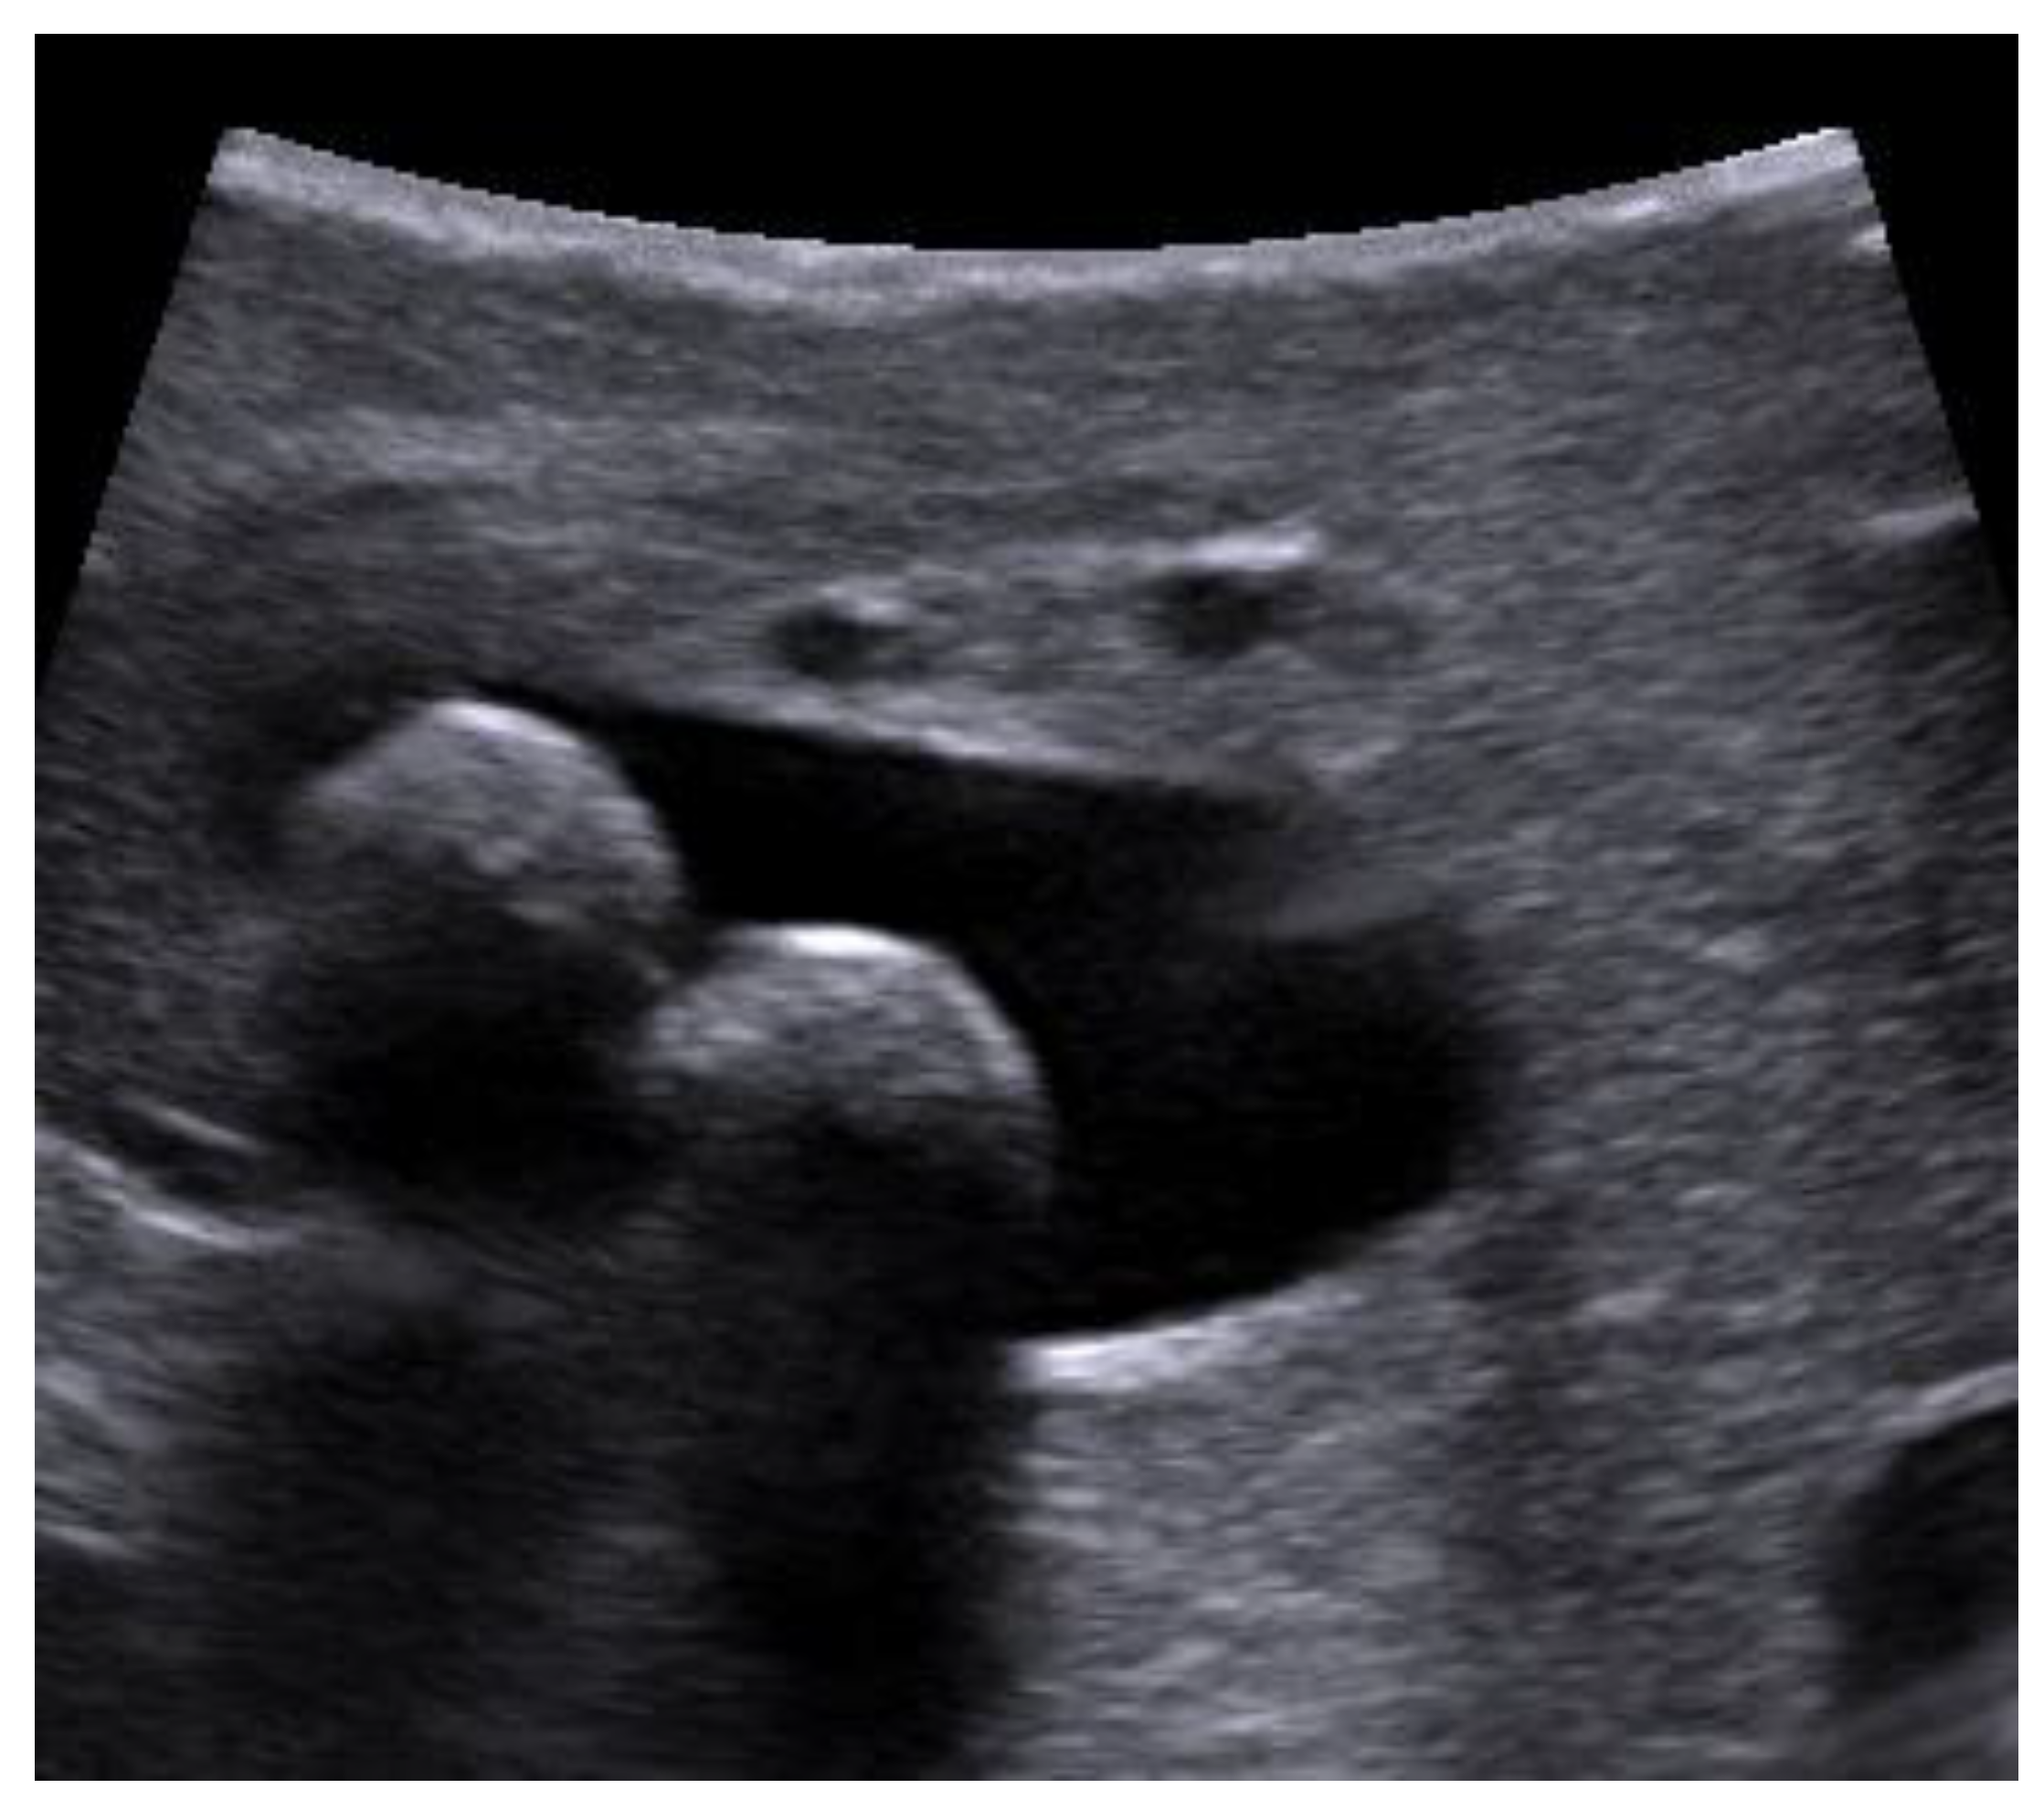

An ultrasound probe was inserted in the abdominal cavity through the epigastric trocar. Once the fundus part of the gallbladder was lifted over the liver, scanning began with a gallbladder examination. The common hepatic duct and common bile duct were scanned when the LUS probe was placed on the superior edge of the hepato-duodenal ligament and slid inferiorly to the distal end of the bile duct (Figure 1).

Figure 1. Laparoscopic ultrasonography (LUS) probe on the proximal part of the hepato-duodenal ligament. (photo by the author).